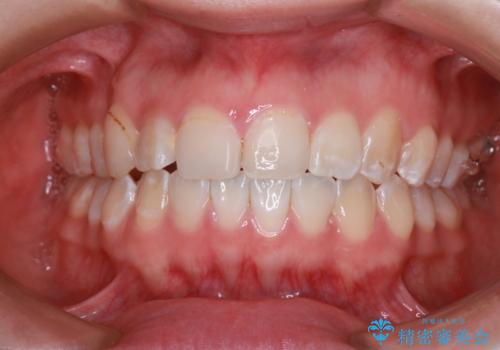

【インビザライン】八重歯が気になる

- 乳歯を抜歯してスペースを確保し八重歯の改善を行いました。

インビザラインをしっかり使用していただいたので、きれいな歯並びになりました。